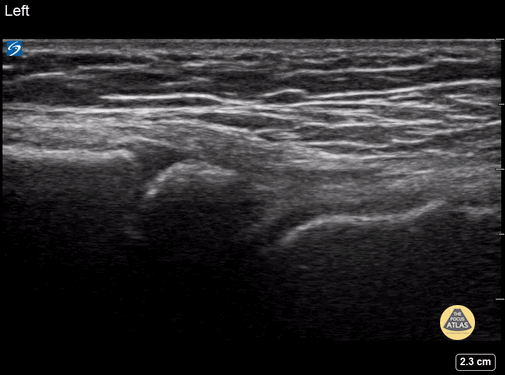

5y female presenting with swelling, redness, and limp to the R foot. Contralateral normal side imaged for comparison. The normal tibiotalar joint in the long axis is seen here. Since the patient skeletally immature, the distal tibial physis can also be seen. Contributor: Matthew Moake, MD PhD